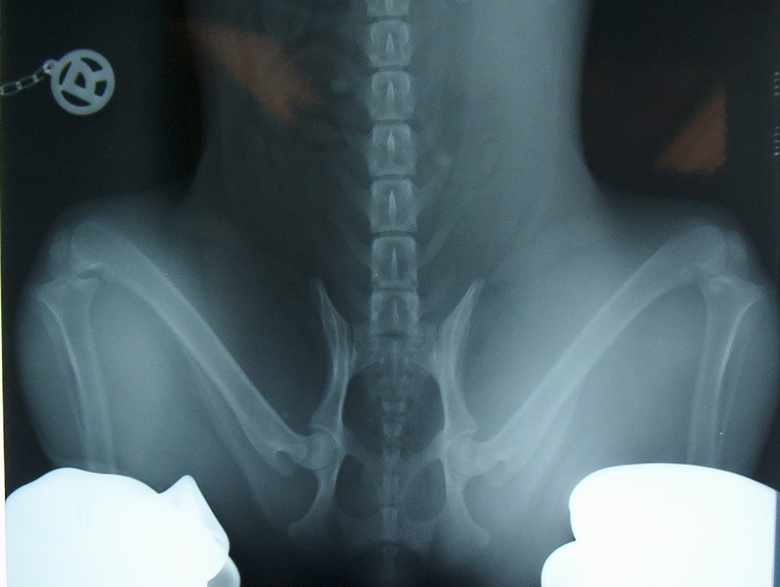

HD-Röntgenuntersuchung

Von Jamilah's Hüftgelenken wurden zwei Röntgenaufnahmen erstellt.

Sinn der Untersuchung ist es, auszuschließen, dass Jamilah eine vererbliche Hüftgelenks-Dysplasie hat. Um die geforderten Aufnahmen erstellen zu können war es notwendig, Jamilah in eine Narkose zu versetzen.

Gemäß der Zuchtordnung des BKD wurde eine Aufnahme in gestreckter und eine in gebäugter Haltung erstellt.

Gebeugte Haltung